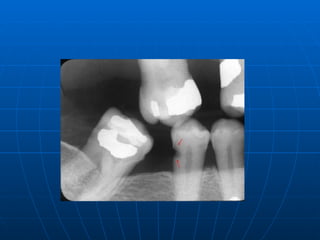

It is believed that bite wing and OPG radiographs along with noninvasive adjuncts like fiber optic  transillumination (FOTI),laser luminescence, electrical resistance method (ERM) are used for diagnosis these occlusal lesions. These lesion are not associated with microorganisms different to those found in other carious lesion.  These carious lesion seem to increase with increasing age. Occult carious lesion are usually seen with low caries rate which is suggestive of increase fluid exposure.

It is believed that  increased fluid exposure encourages remineralization  and slow down progress of the caries in the pit and fissure enamel while the cavitations continues in dentine, and the lesions become masked by a relatively intact enamel surface. These hidden lesions are called as  fluoride bombs or fluoride syndrome. Recently it is seen that occult caries may have its origin as pre-eruptive defects which are detectable only with the use of radiographs.

It is believedthat bite wing and OPG radiographs along with noninvasive adjuncts like fiber optic transillumination (FOTI),laser luminescence, electrical resistance method (ERM) are used for diagnosis these occlusal lesions. These lesion are not associated with microorganisms different to those found in other carious lesion. These carious lesion seem to increase with increasing age. Occult carious lesion are usually seen with low caries rate which is suggestive of increase fluid exposure.

It is believedthat increased fluid exposure encourages remineralization and slow down progress of the caries in the pit and fissure enamel while the cavitations continues in dentine, and the lesions become masked by a relatively intact enamel surface. These hidden lesions are called as fluoride bombs or fluoride syndrome. Recently it is seen that occult caries may have its origin as pre-eruptive defects which are detectable only with the use of radiographs.